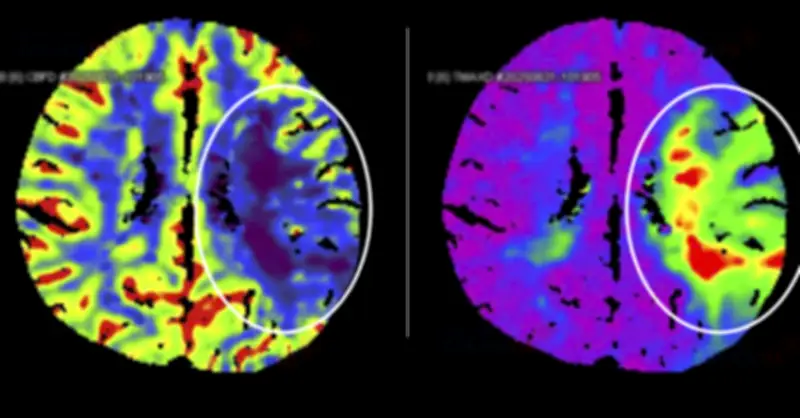

Quá trình điều trị bao gồm nhiều bước phức tạp, từ chẩn đoán hình ảnh chi tiết đến các thủ thuật can thiệp mạch máu. Các bác sĩ sử dụng kỹ thuật tiên tiến như chụp cộng hưởng từ và nội mạch để xác định chính xác vị trí tắc nghẽn và thực hiện các biện pháp giải phóng cục máu đông. Sự phối hợp nhịp nhàng giữa các chuyên gia từ nhiều khoa khác nhau đã đóng vai trò quan trọng trong thành công của ca mổ.